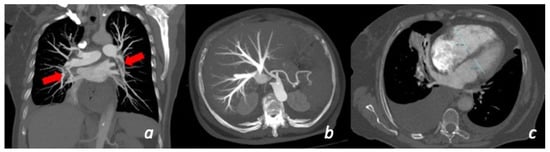

Figure 6.

Patient with chest pain and dyspnea for more than 10 days with recent worsening of symptoms. CT shows the presence of massive bilateral pulmonary thrombo-embolism (red arrows) in the right and left lower lobe pulmonary artery (a). Secondary overload of the right-side circulation: enlargement of the right ventricle (c) and secondary tricuspid insufficiency (b).